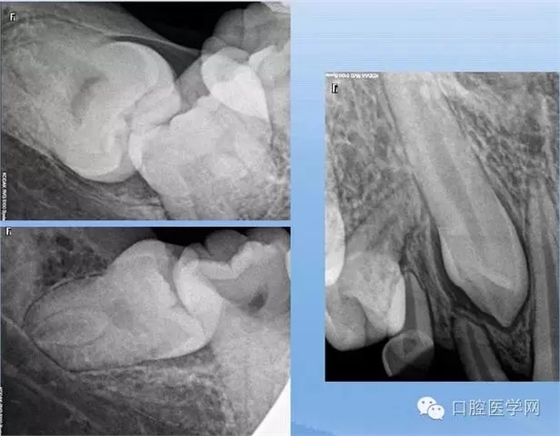

牙根異常(數(shù)目異常、形態(tài)異常)

X線表現(xiàn):恒磨牙及上頜雙尖牙多見(jiàn),注意頰舌側(cè)根重疊雙層牙周膜影響,確定牙根變異的類(lèi)型和程度。